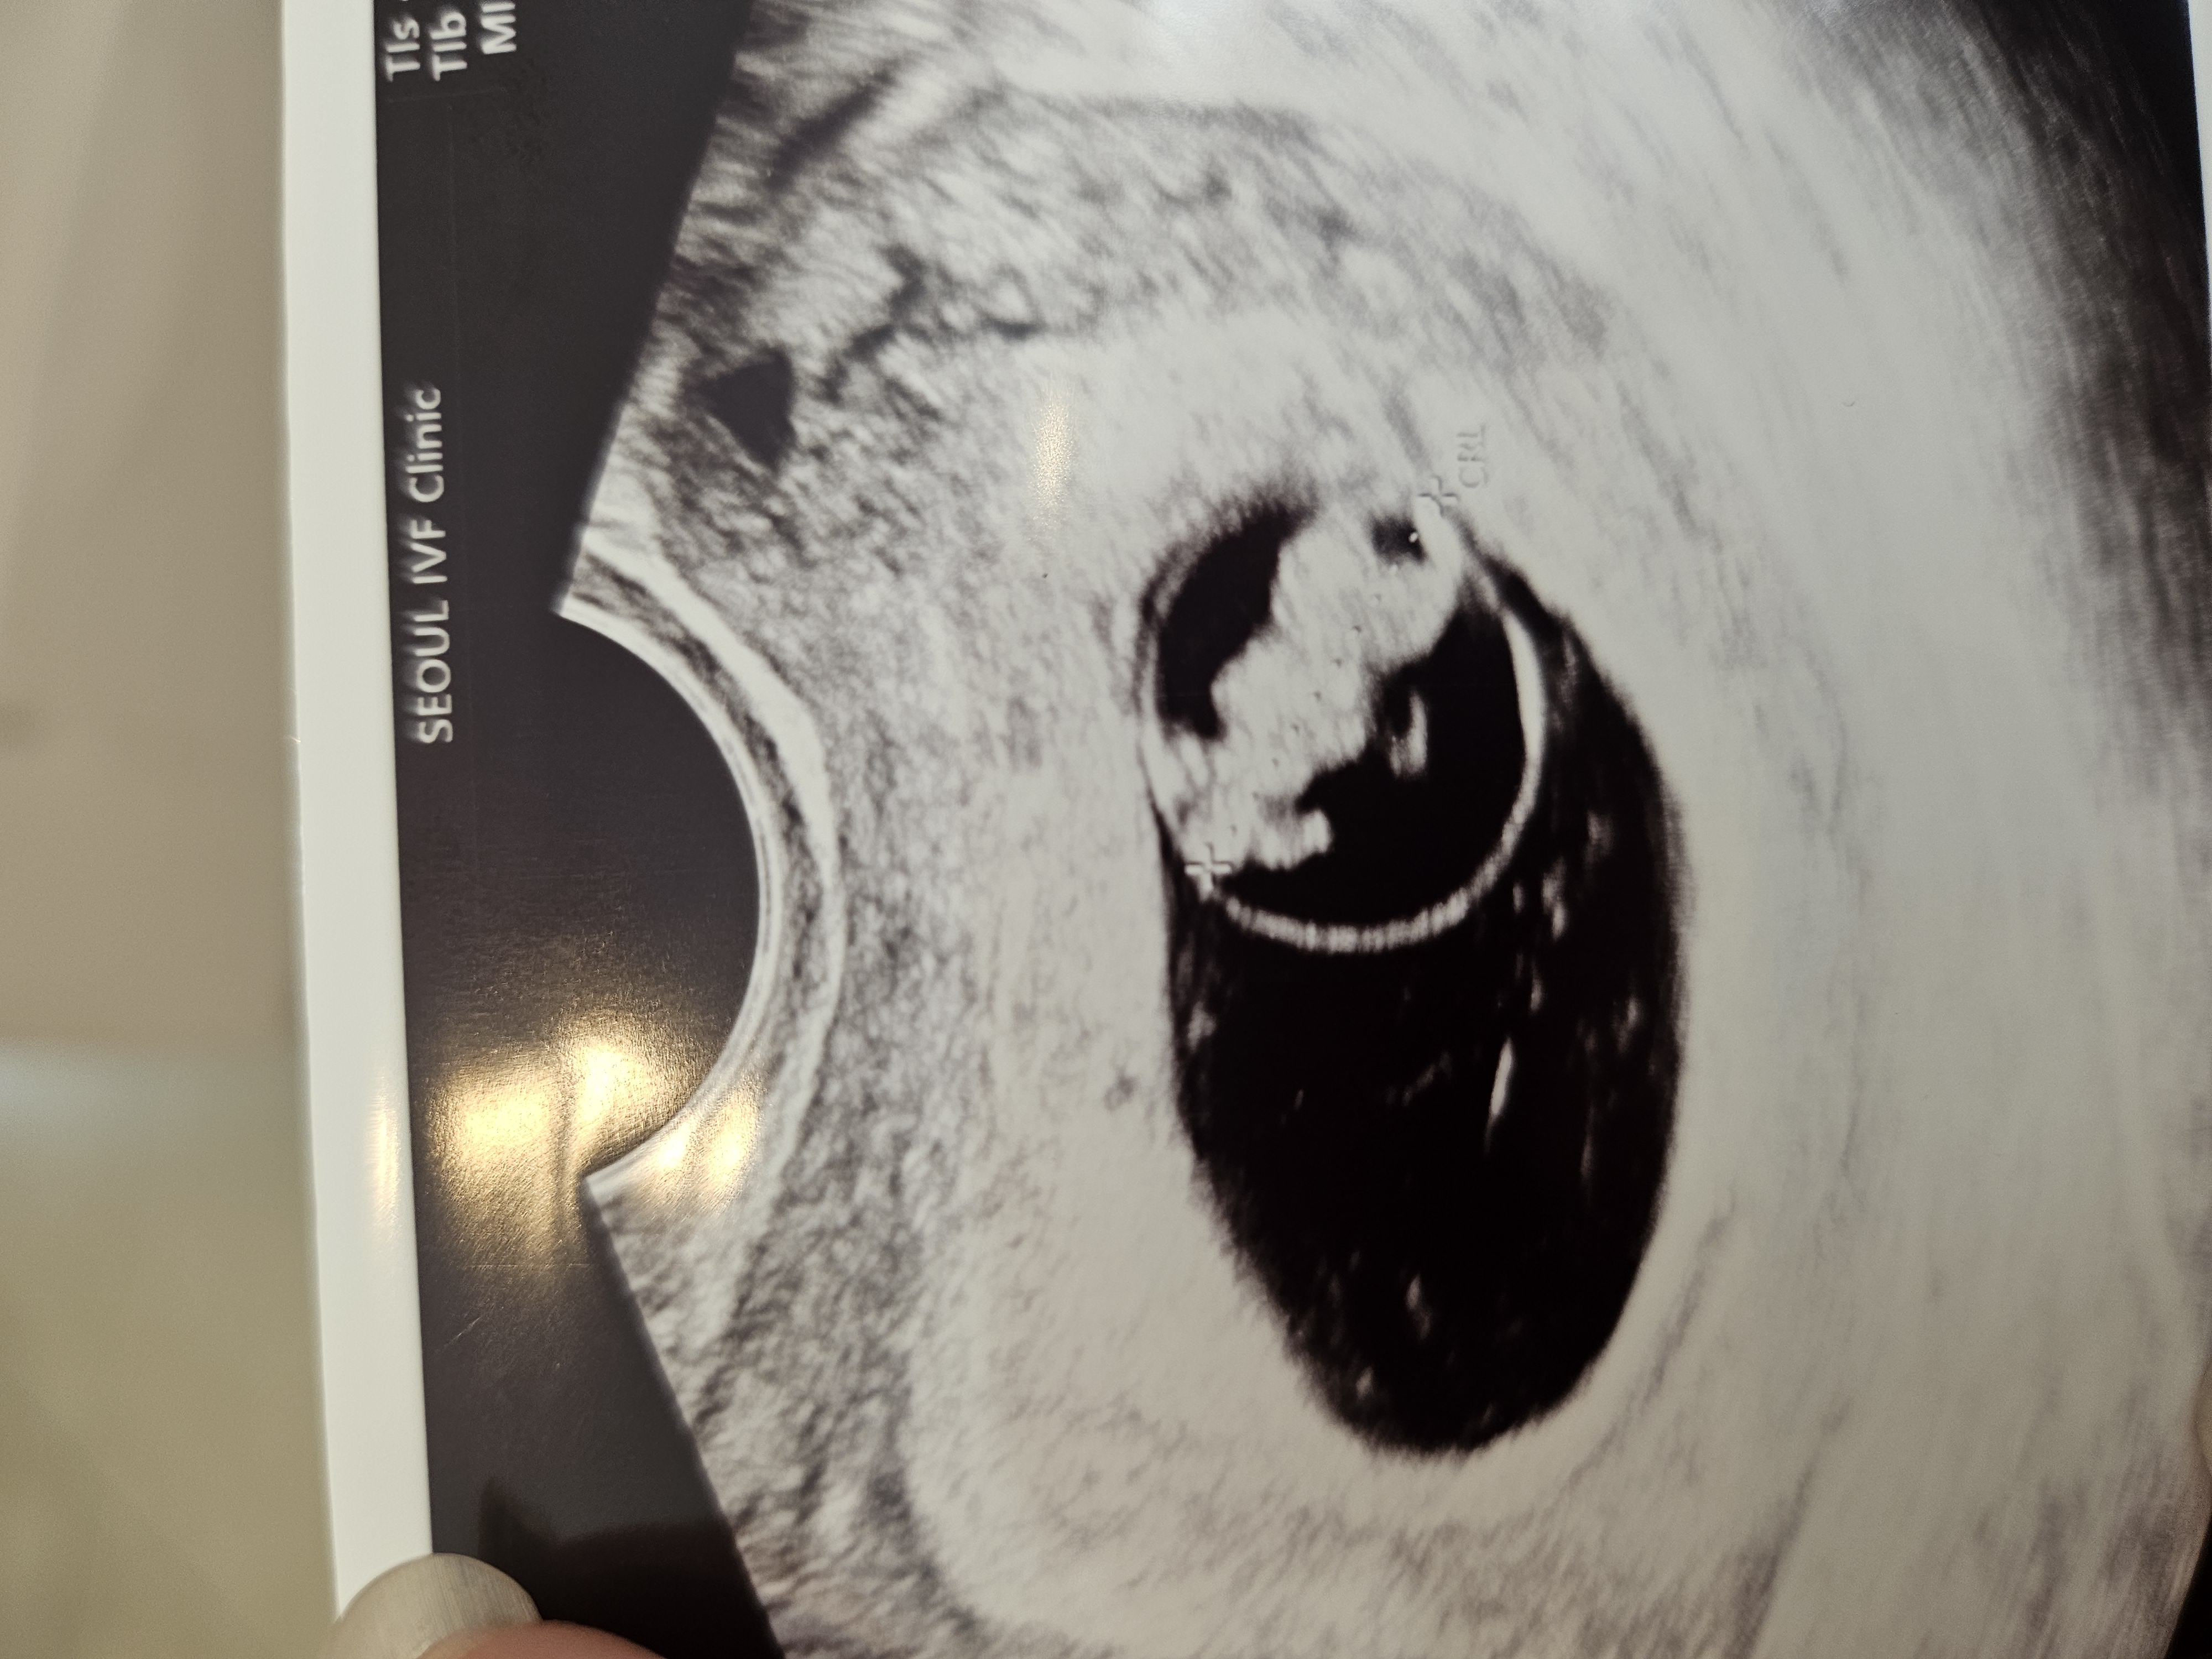

| 가슴 떨리는 임신 이야기를 공유해 주세요. | 첫째도 서울아이비에프여성의원에서 시험관으로 임신에 성공했고, 둘째 역시 이유정 원장님과 함께 다시 시작하게 되었습니다. 제 몸 상태와 컨디션에 맞춰 치료를 진행했고, 큰 수술과 치료 이후라 걱정이 많았지만 감사하게도 한 번에 임신에 성공할 수 있었습니다. |

| 치료 도중 느꼈던 가장 기뻤던 순간과 절망적인 것들은 무엇인가요? 잊지 못할 경험이 있나요? | 임신 확인을 했던 순간이 가장 기뻤습니다. 몸이 아픈 뒤 시작한 시험관이라 ‘과연 될까’ 하는 두려움이 컸지만, 그 모든 걱정을 덜어주는 결과였고 지금도 잊지 못할 순간으로 남아 있습니다. |